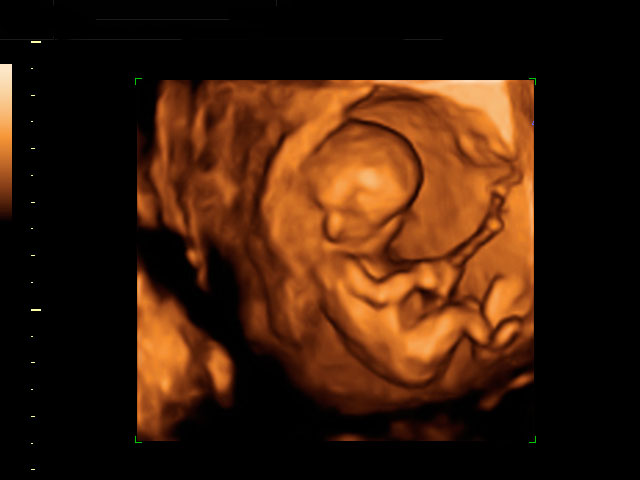

Ecografía 4D semana 12: Bebé moviendo brazos y piernas

Destaca la gran vitalidad del feto

La ecografía 4D muestra un bebé de 12 semanas de gestación moviéndose con gran vitalidad dentro del útero materno. Se percibe perfectamente que el feto tiene formadas todas sus estructuras básicas, a falta de que maduren a lo largo del embarazo.

Ecografía en 4D de bebé de 12 semanas moviendo brazos y piernas

La vitalidad del bebé es increíble. Mueve brazos y piernas con energía, como si estuviera nadando, o haciendo un "sprint" final. En realidad está apoyado en la pared uterina de su madre. Se perciben las estructuras básicas del feto con gran claridad: cabeza, aún muy grande respecto al cuerpo, tronco y extremidades. Este movimiento es uno de los signos de vitalidad fetal que los ecografistas siempre evalúan en sus exploraciones.